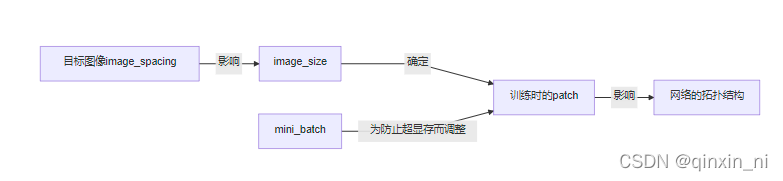

2.4.4 网络拓扑、patch_size 、batch_size的自适应性

- 寻找一个合适网络拓扑结构对于得到一个优秀的分割表现相当的重要。在一定的GPU显存的限制下,nnUNet优先选择一个大的patch_size,更大的patch_size会获取到更多的上下文的信息,这显然能提高模型的表现。但是,相对应的代价就是要减小batch_size(同时很大肯定占显存),而减小batch_size就会使反向传播的梯度下降变得不稳定(有时候学的好有时候学的坏,因为输入的不同batch的数据差距大)。为了提高训练的稳定性,我们提出一个值为2的mini_batch同时在网络训练时加入一个大的动量项(蓝图参数里有)。

- 图像的spacing也被作为自适应的一部分去考虑:

下采样的操作很可能只在某个特定的轴上进行操作,3D U-net的卷积核可能对特定的平面进行操作(伪2D)。所有U-Net配置的网络拓扑都是根据重新采样后图像尺寸的中值以及重新采样到的目标间距来选择的。附录E.1有一个流程图展示了这个自适应的流程。接下来会探讨更多的网络结构模板的自适应的细节,通常都不会以昂贵的计算力为代价。因为GPU的内存消耗估计是基于feature_map的大小,而这个适应过程和feature_map的关系很小,所以不需要GPU参与这个进程。

我们进行一次“管道指纹”的设计,要么就是人为的设置,要么就是利用各个“数据指纹”之间的隐藏关系进行设置。结果可能就是,对于一个数据集来说优化的效果很好,而对于其他数据集可能没有什么作用,对于一个新的数据集,就需要人为的不断的进行再建计划和再次优化。比如图片的尺寸会影响patch_size,patch_size会反过来影像网络的拓扑结构(下采样的次数和卷积核的尺寸等),而网络的拓扑结构将再次影响其他的超参数。